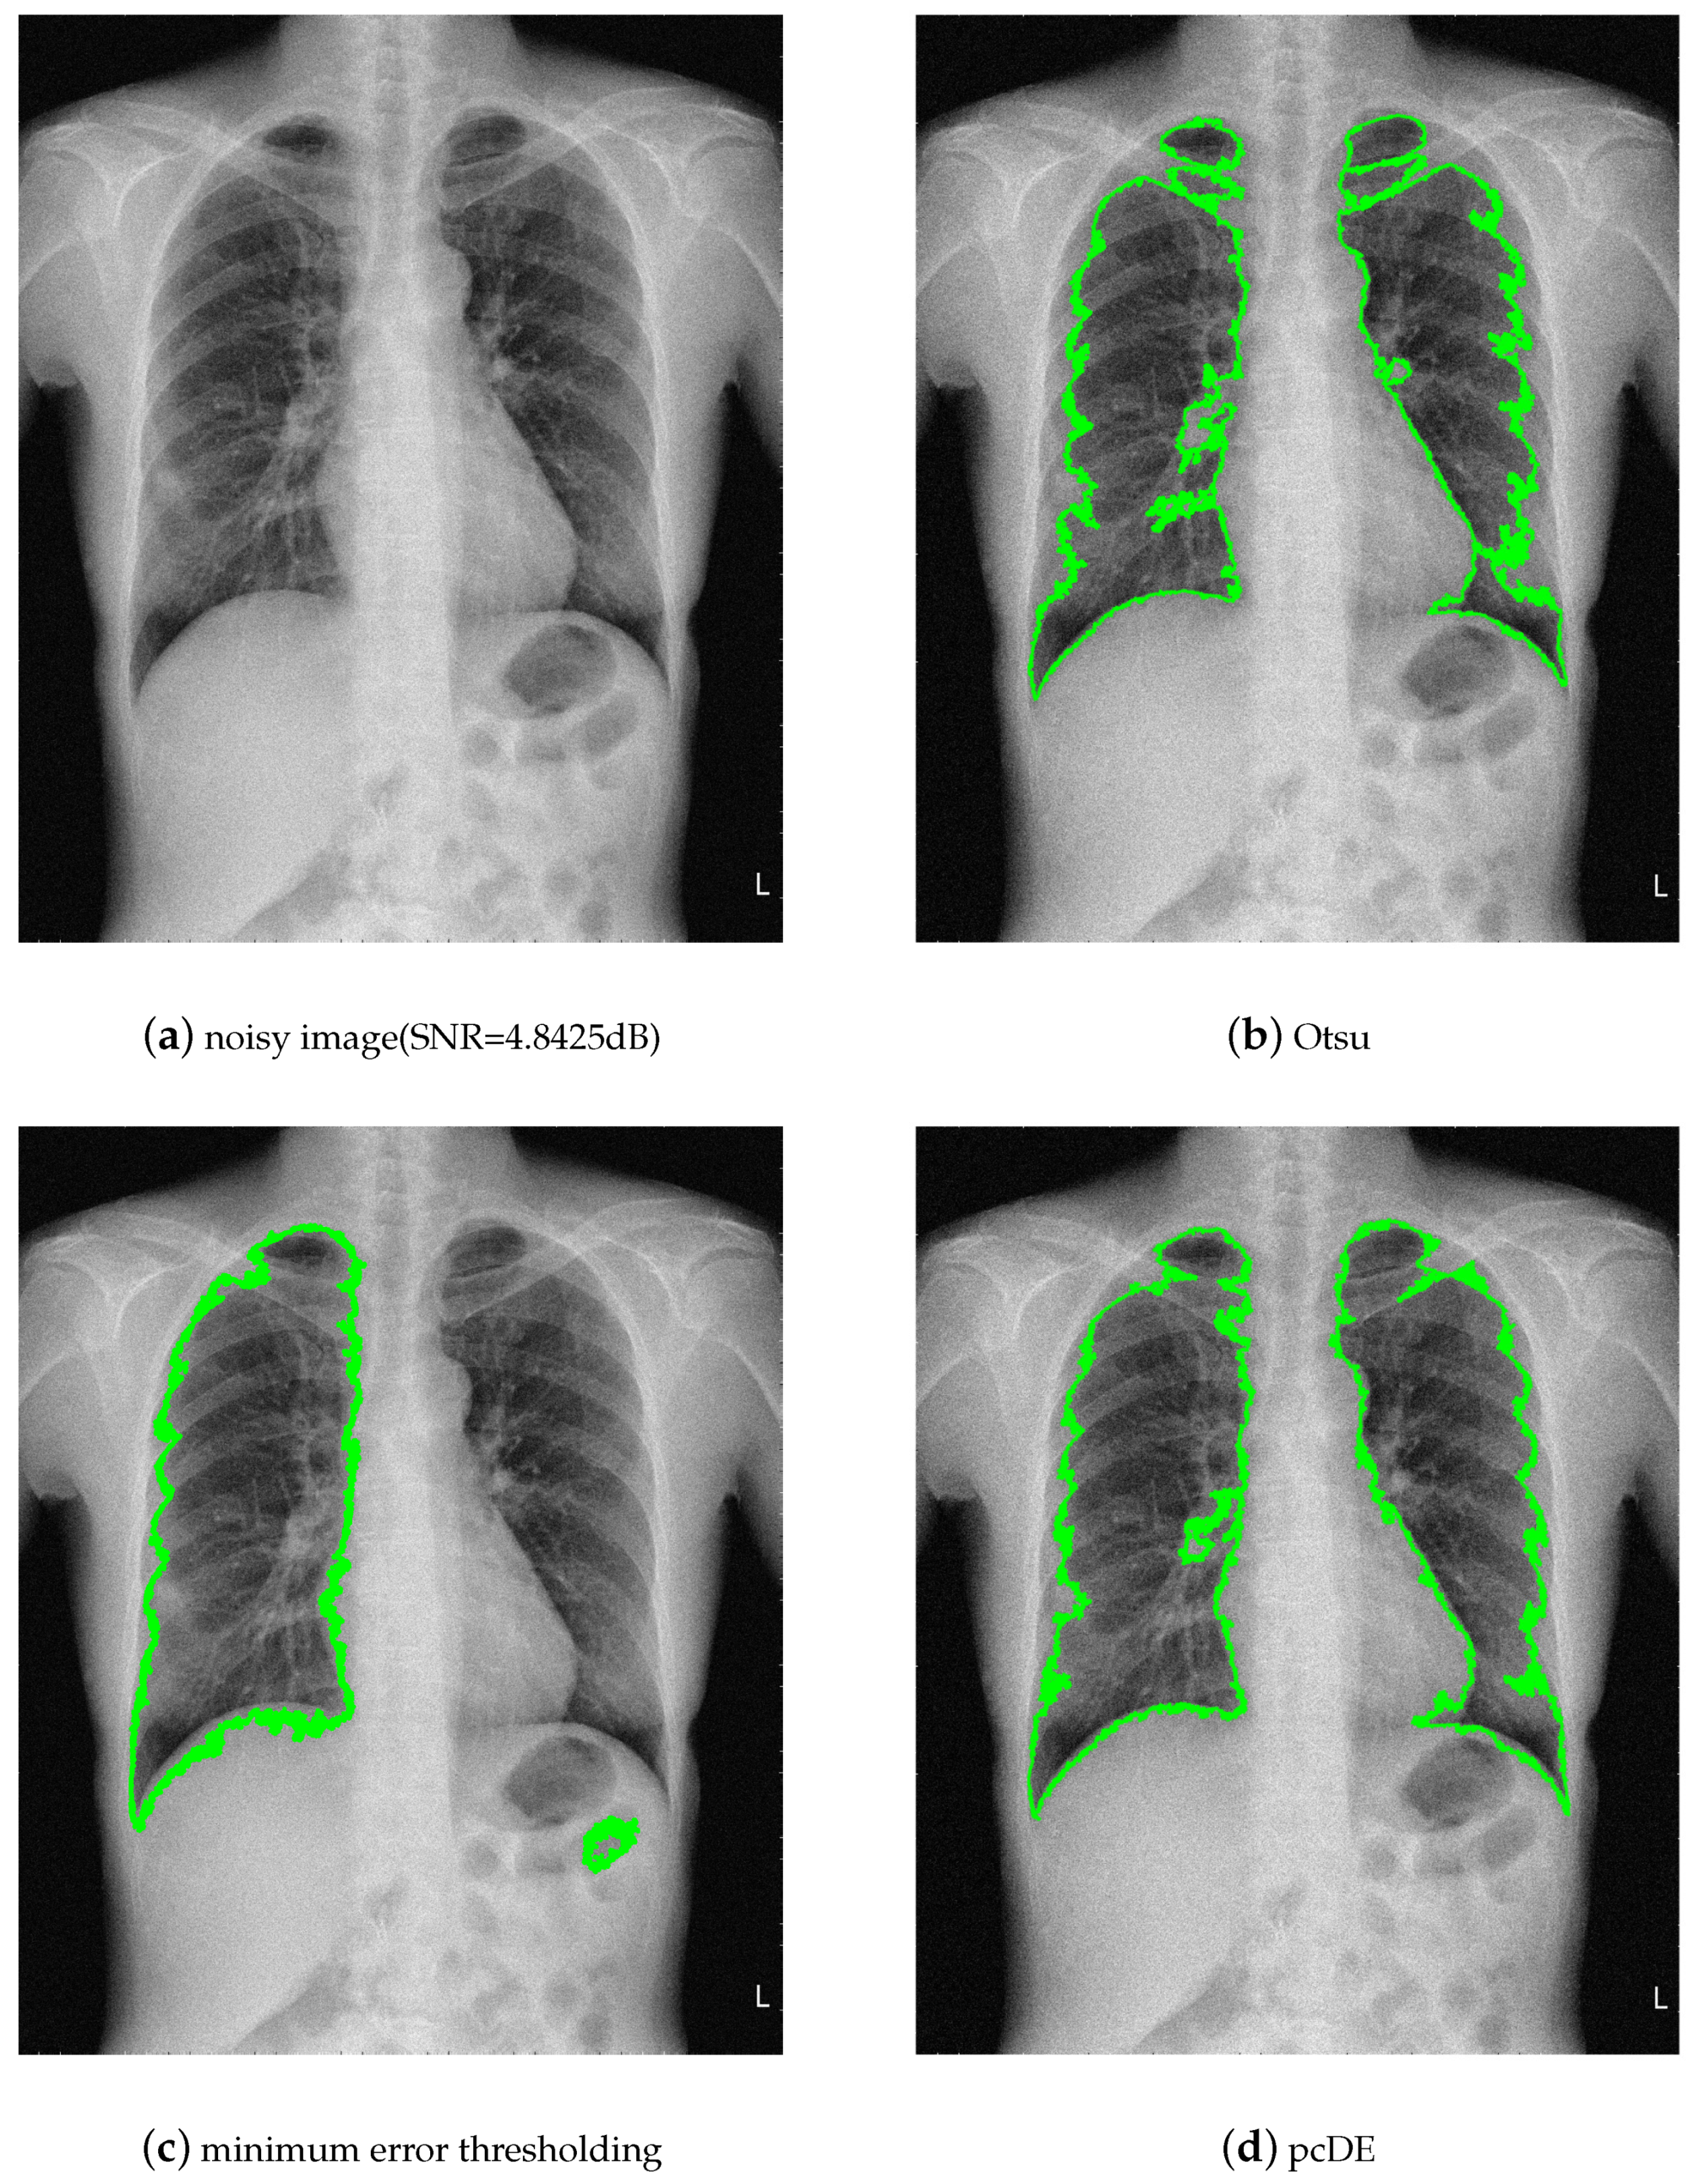

- Image preprocessing. Enhance the contrast of the image to achieve better segmentation.

- Calculate the optimal threshold for image segmentation through different methods to get the binarized image.

- Use morphological methods to process images to extract targets.

- Mark target contour.

- : Represent the result of ground truth segmentation (Figure 13).

- : Represent the result of algorithm segmentation.

| Segmentation Method | Original Image | Noisy Image |

|---|---|---|

| Otsu | 0.9210 | 0.9531 |

| minimum error thresholding | 0.9732 | 0.9093 |

| pcDE | 0.9738 | 0.9684 |